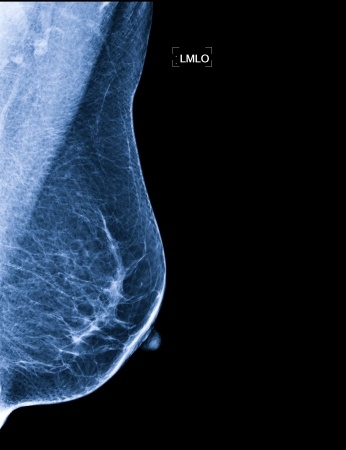

Nowe wytyczne ASCO leczenia zaawansowanego HER2-ujemnego raka piersi

2 września w Journal of Clinical Oncology opublikowano nowe wytyczne ASCO (ang. American Society of Clinical Oncology) pomagające w wyborze optymalnej terapii dla chorych na HR2-ujemnego raka piersi